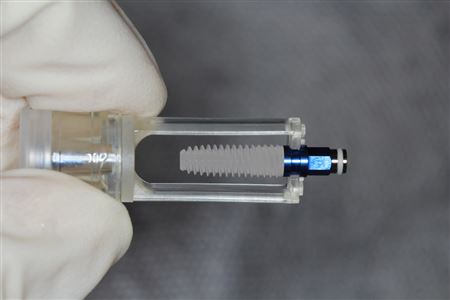

اگر پزشک نتواند در مورد سقط جنین یا حاملگی خارج رحم نظر قطعی بدهد، ممکن است با استفاده از عمل لاپاراسکوپی، لولههای رحم را با دقت بیشتری بررسی کند. در این عمل، دوربین کوچکی از طریق یک برش ریز وارد شکم شما میشود. 2

در مواردی که حاملگی خارج از رحم زود تشخیص داده شود، چنانچه اندازه جنین هنوز کوچک و حاملگی به طور واضح در خارج از رحم باشد، میتوان از درمان دارویی استفاده کرد. درمان غیر جراحی یک حاملگی خارج رحمی بدون پارگی، استفاده از نوعی داروی ضد سرطان به نام متوترکسات است که داخل مجرای فالوپ تزریق می شود و مولکول های آن رشد سلولی تخمک را متوقف می کنند و سلول های موجود را از بین می برند.این دارو که به گونه تزریق داخل وریدی در بیمارستان یا درمانگاه بیماران سرپایی، تجویز می شود میتواند با بی حسی عمومی بدن انجام شود ولی نیازی به بستری شدن نیست. مریض همان روز میتواند بیمارستان را ترک کند ولی باید حدود پانزده روز بعد، دوباره برای معاینه مراجعه کند.

درمان جراحی:محافظت کننده

جراحی میتواند به صورت لاپاراسکوپی یا لاپاراتومی( باز کردن شکم) صورت گیرد.درصورتی که بتوان این نوع بارداری را در مرحله های نخست تشخیص داد و اندازه آن زیر 4 سانتیمتر باشد، میتوان از جراحی لاپاراسکوپی استفاده کرد.